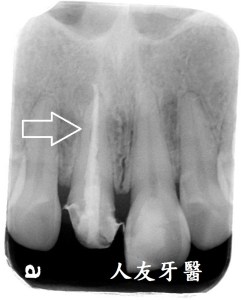

根尖病變一直長膿包還有救嗎?